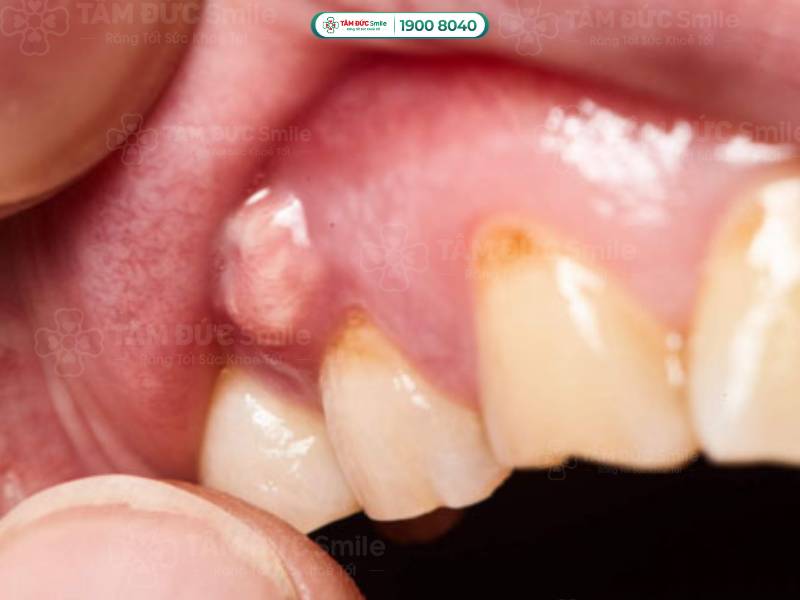

1.1.2. Áp xe chóp răng (áp xe chân răng)

Áp xe được hiểu là tập hợp mủ được hình thành từ các tế bào bạch cầu chết, vi khuẩn và những mảnh mô vụn. Vấn đề áp xe chóp răng bắt đầu từ tủy răng và kết thúc ở phần chóp chân răng.

Vấn đề áp xe chóp răng bắt đầu từ tủy răng và kết thúc ở phần chóp chân răng

Phần lớn các trường hợp áp xe chân răng là do sâu răng, răng bị sứt mẻ nặng gây tổn thương tới tủy. Ngoài ra, người bệnh viêm nướu, viêm nha chu cũng có nguy cơ bị áp xe chóp răng cao hơn. Bởi vì vi khuẩn phát triển dần vào chóp răng, gây viêm nhiễm, theo thời gian tiến triển thành áp xe.

Chứng áp xe chóp răng thường khó nhận biết bằng mắt thường. Người bệnh có những biểu hiện dưới đây nên đến thăm khám ở các cơ sở y tế để được chẩn trị chính xác:

- Phần lợi dưới chân răng bị sưng; khi soi gương, bạn có thể thấy hạt mủ tụ ở phần chân răng gây đau.